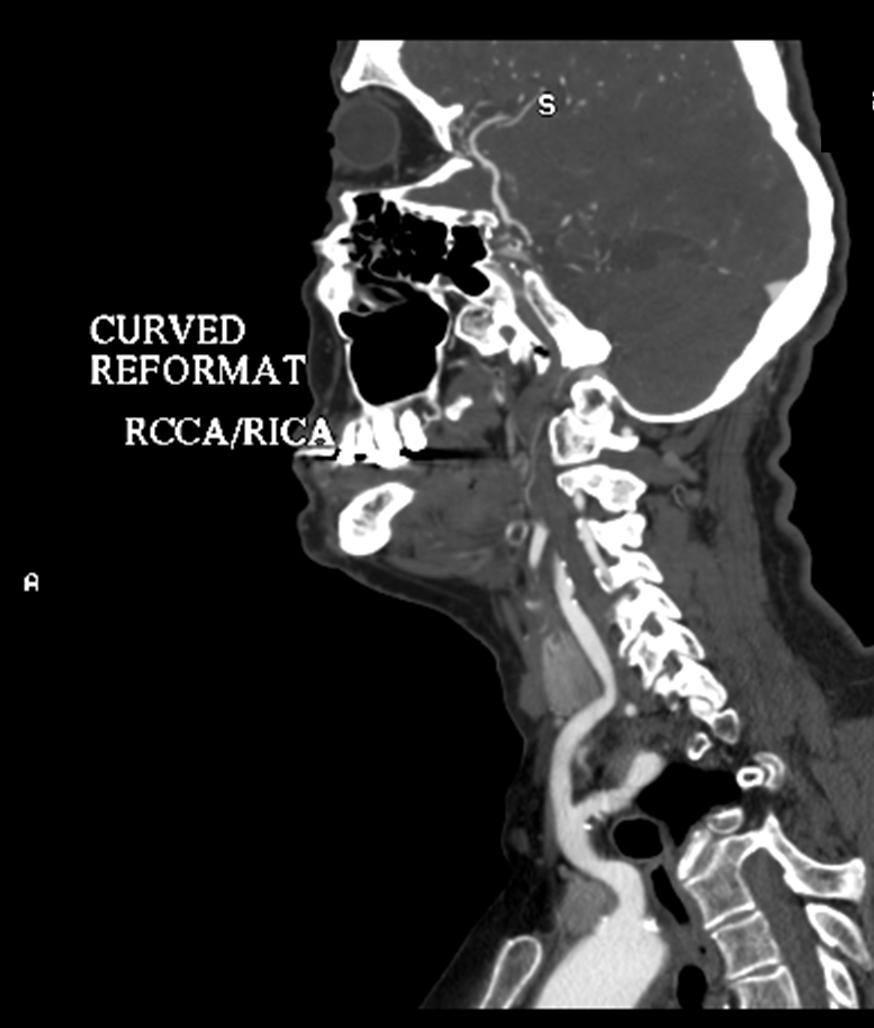

CTA can also show the occlusion and its extent.